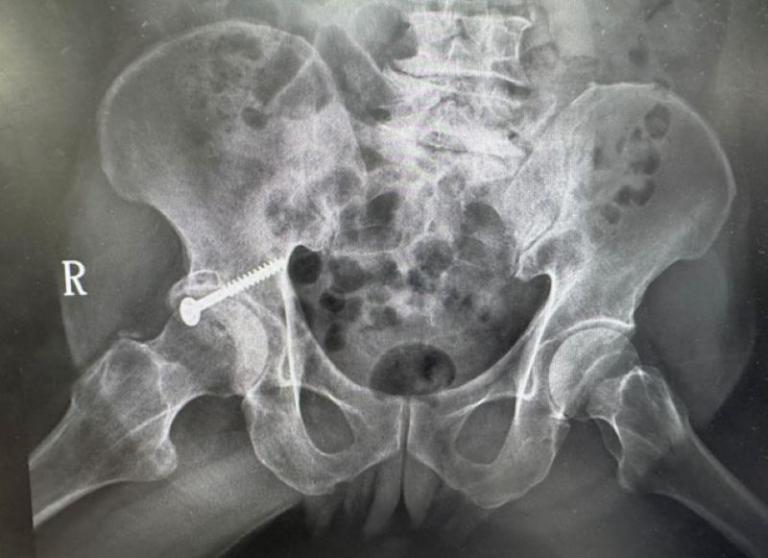

一名76歲老翁多年前因髖臼骨折接受手術,術後留下垂足與步態異常,造成長期行動不便,導致外傷性退化性髖關節炎,連上廁所與行走都成為挑戰,經新竹臺大分院骨科團隊詳細評估並與病人充分溝通後,決定採用「

前側入路(DAA)」人工髖關節置換手術,避開之前的手術區域,病人術後當天即可床邊如廁並下床行走,疼痛顯著減輕,展現微創技術在高齡手術中的安全與高效,成功改善長年困擾。

▲新竹臺大分院骨科部團隊施行前側入路人工髖關節置換手術,避開之前的手術區域,降低併發症風險,術後恢復良好。(圖/記者蔣彤雲攝)